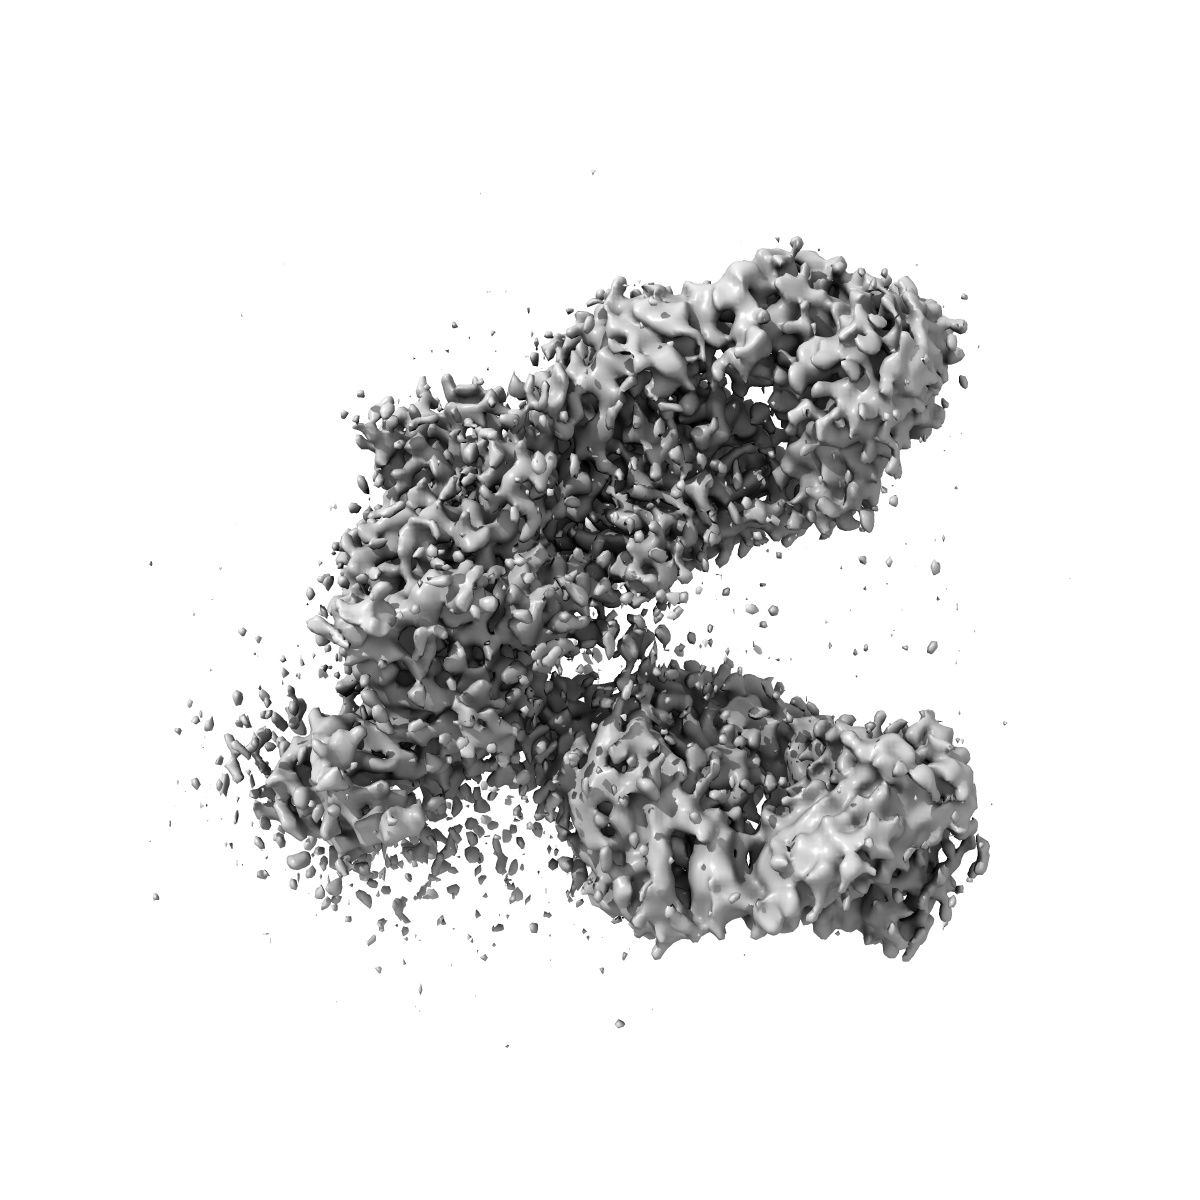

Cryo-EM structure of engineered hepatitis C virus E1E2 ectodomain in complex with antibodies AR4A, HEPC74, and IGH520

Sample Organism: Homo sapiens, synthetic construct, Hepacivirus C

Sample: HCV E1E2 ectodomain in complex with AR4A, HEPC74, and IGH520

Structure of engineered hepatitis C virus E1E2 ectodomain in complex with neutralizing antibodies.

Metcalf MC, Janus BM , Yin R , Wang R, Guest JD, Pozharski E , Law M , Mariuzza RA , Toth EA , Pierce BG , Fuerst TR , Ofek G

(2023) Nat Commun , 14 , 3980 - 3980